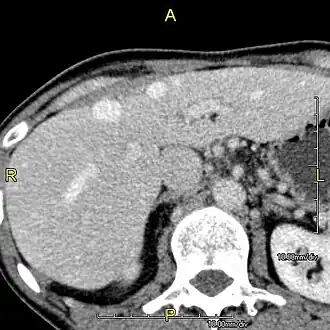

A CT scan in which the liver and portal vein are shown

Phase contrast CT image. Contrast is perfusing the right liver but not the left due to a left portal vein thrombus.